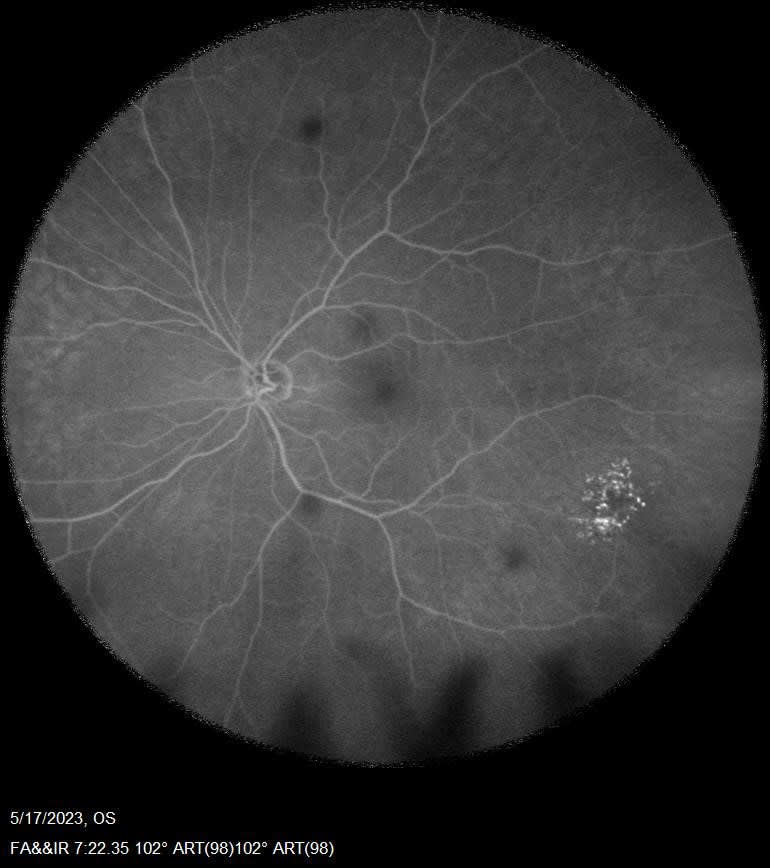

The team utilized various imaging techniques to further study these findings. Optical coherence tomography (OCT) imaging confirmed the cystic character of the lesion, revealing structurally normal overlying retinal tissue (Figure 1). Fluorescein angiography (FA) displayed hyperfluorescence with late staining, yet no signs of leakage were detected (Figure 2). After these 2 diagnostic tests, magnetic resonance imaging (MRI) of the brain was recommended to exclude any potential intracranial involvement.